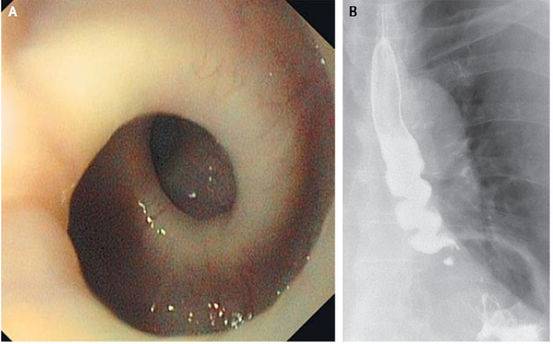

13、专门在吃饭的时候作妖的食道

瑞士一名87岁女性因每次吞咽感到疼痛而就诊。

X光片发现她的食道在她每次进食的时候都会扭转成螺旋形。这个症状导致她在数月内体重下降5公斤。

这种病症非常少见但是并非不能解释,美国芝加哥西北纪念医院的医生认为,这是由于肌肉痉挛引起的。进食正常的情况下,途径上的肌肉会有规律的收缩和舒张,但是这名妇女的食道在收到刺激的时候会收缩。

目前对这种症状没有解决方案。

这个案例发表在2014年5月的扭英上。